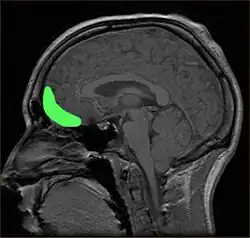

![]() Approximate location of the OFC shown on a sagittal MRI | |

Orbitofrontal cortex highlighted in green on sagittal T1 MRI images